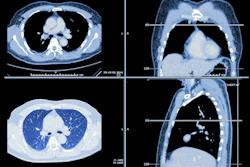

Low-dose CT (LDCT) for lung cancer screening occasionally finds other malignancies outside the lungs, according to a study published October 12 in the Journal of the American College of Radiology.

The strengths of lung cancer screening with LDCT have been validated by many studies, and its cost-effectiveness is considered reasonable when it is offered to appropriate patient populations. But sometimes LDCT used for lung screening identifies other malignancies, and the cost of working up these incidental findings has remained unclear, the team noted.

Chintanapakdee's group conducted a study that included 7,414 LDCT exams performed between June 2014 and December 2019 on 4,160 patients as part of a lung cancer screening program, identifying any patients with indeterminate extrapulmonary lesions and tracking the diagnostic workup, management, and outcomes of these findings. The team then estimated costs related to evaluating these incidental findings using 2020 total facility relative value units and the 2020 Medicare conversion factor.